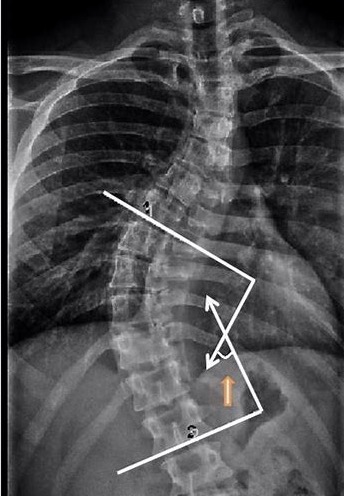

- Cobb's angle���Ʋ��ǣ� ���Ǽ�������������� ��2020-02-27

- Cobb�� ���壺Cobb�DZ�������������ȷ�����ټ�������Ľ�չ��Dr John Cobb ��1948�귢�������ַ������������壺Cobb�ǰ���ҽ��������Ҫʲô�������ơ� .....